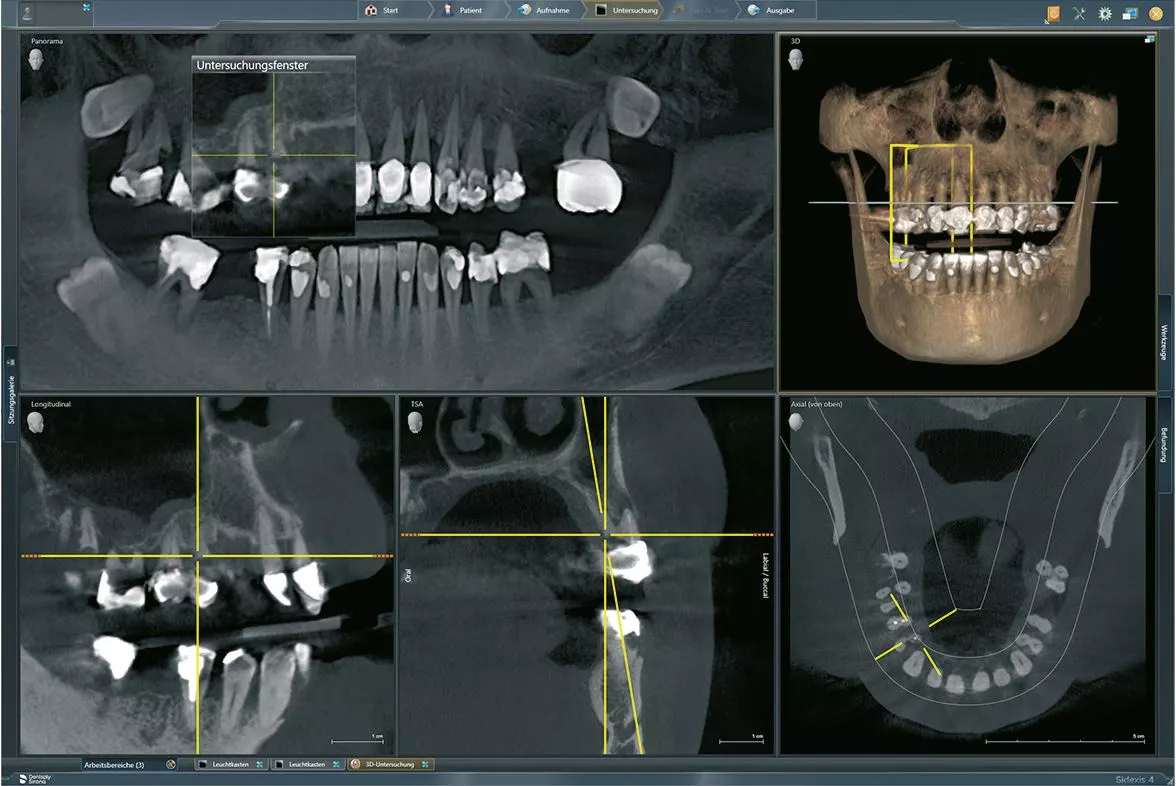

Daher haben sich in der Vergangenheit zum Beispiel Zentren für die Durchführung der Implantatplanung etabliert [6]. Für die prothetisch orientierte Planung benötigt das Planungszentrum neben den Informationen über die gewünschte Position und Anzahl der Implantate und die Unterlagen über das Knochenangebot, die anatomische Struktur und die Bißlage. Diese Daten können über konventionelle Abdrücke oder intraorale Scans der Kiefer, sowie mittels dreidimensionaler Röntgenaufnahmen zur Verfügung gestellt werden (Abb. 1-3). Mit diesen Unterlagen kann dann die Implantatplanung mit Umsetzung einer Navigationsschablone sowie die Herstellung eines Provisoriums erfolgen [4].

Die weitere Kommunikation erfolgt dann über das Nachrichtenfenster im Kommunikationsportal (Abb. 6). Hier können erste Entwürfe als Screenshots gesendet oder Fragen beantwortet werden. Nach Abschluss aller Fragen erfolgt dann der finale Vorschlag für die Implantatplanung, die in einem mehrseitigen PDF, die räumliche Darstellung der Implantate im Planungsprogramm, zeigt (Abb. 7).

Zur genauen Abstimmung kann die Planung über einen Online-Zugriff auf den Planungscomputer mittels eines Screen-Sharingsprogramms zwischen Behandler und Zahntechniker diskutiert werden. Sofern die Planung den Erwartungen des chirurgisch tätigen Zahnarztes entspricht, kann der Vorschlag angenommen und für die Produktion freigegeben werden (Abb. 8). Die Produktion der Bohrschablone und des Provisoriums erfolgt dann im Fertigungszentrum. Nach Fertigstellung werden alle benötigen Systemkomponenten mit den zahntechnischen Werkstücken versandt.